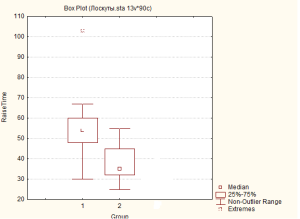

Так, середня тривалість часу, що було витрачено на препарування клаптя в групі 1, зі стандартним передопераційним обстеженням, склала – 54 хв. з 95% ДІ [[50;60]] (діапазон, 30-103 хв.). В групі 2, з модифікованим передопераційним обстеженням, цей показник склав – 35 хв. з 95% ДІ [[33;45]] (діапазон, 25-55 хв.), що вказує на статистично високозначуще (p=0,000006) зниження тривалості етапу виділення клаптя на судинній живлячій ніжці, що містить єдину домінуючу перфорантну артерію, та заперечує «нульову» гіпотезу (Мал. 5). Дані результати дозволяють стверджувати, що застосування модіфікованої програми передопераційного обстеження, що включає контрастну КТ-ангіографію, дозволяє скоротити час, що витрачається на препарування клаптя за рахунок більш прецизійної та впевненої дисекції.

Мал. 5. Тривалість інтраопераційного етапу виділення клаптя на живлячій судинній ніжці в досліджуваних групах: група 1 – група зі стандартним передопераційним обстеженням; група 2 – група з модифікованим передопераційним обстеженням (ліворуч).